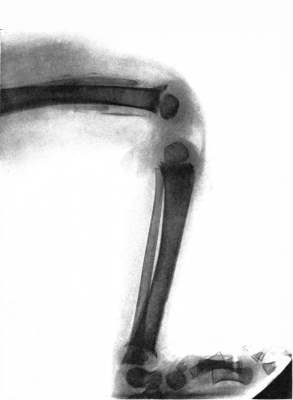

| 6. | Subperiosteal hemorrhage and separation of epiphysis. Roentgenogram | 109 |

| 7. | Complete restitution of epiphysis without deformity. Roentgenogram | 109 |

| 16. | Subperiosteal hemorrhage and separation of epiphysis. Roentgenogram | 192 |

| 17. | Periosteal “tags” and “streamers.” Roentgenogram | 193 |